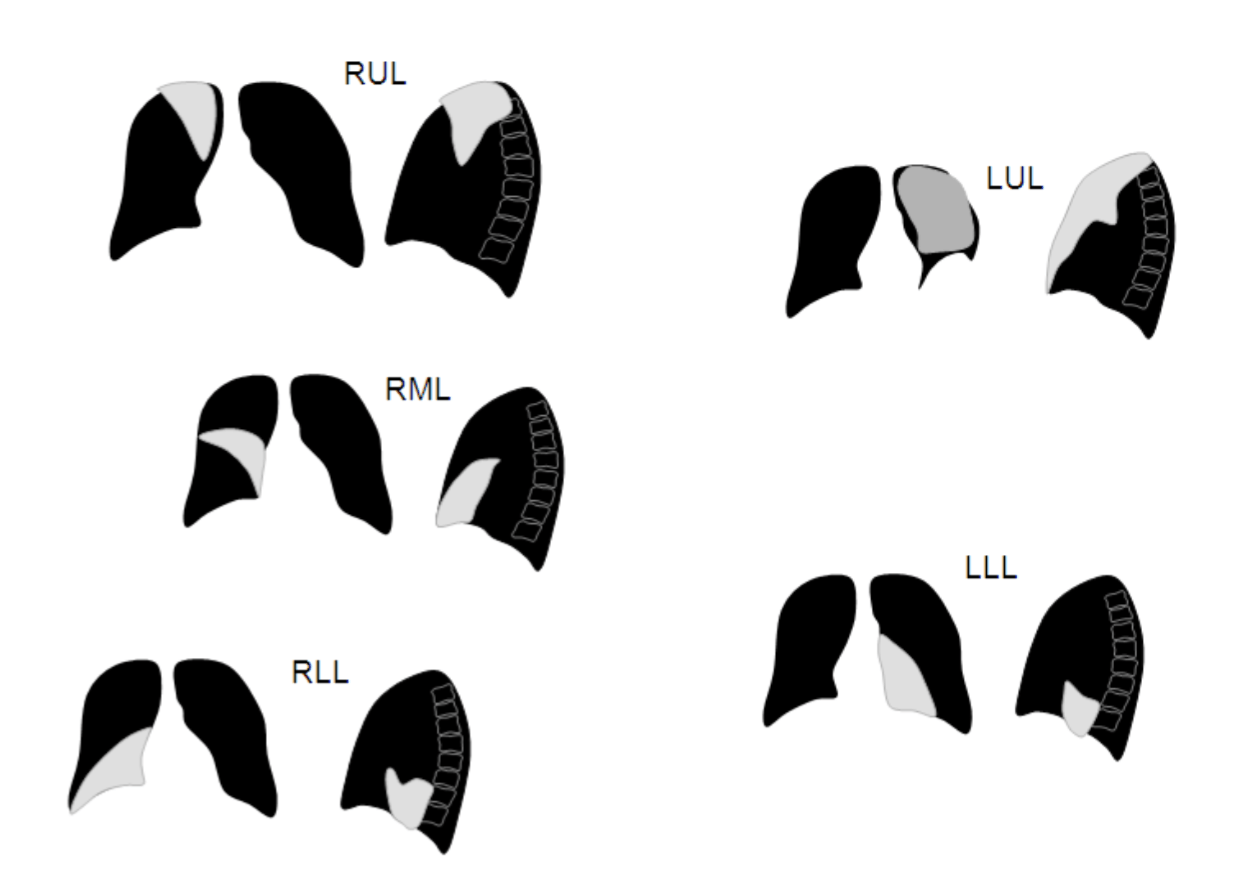

- Lobar atelectasis: given the nature of this condition, any of the 5 lung lobes can be affected.

RIGHT UPPER LOBE ATELECTASIS

The archive below organizes different examples of a right upper lobe atelectasis. It will really be the anatomical location of the finding that will help diagnosis this SPECIFIC subtype of atelectasis. Click on the thumbnails below to view the archive.

RIGHT MIDDLE LOBE ATELECTASIS

The archive below organizes different examples of a left middle lobe atelectasis. It will really be the anatomical location of the finding that will help diagnosis this SPECIFIC subtype of atelectasis. Whats more, this type of atelectasis often obscures the right cardiac border. Click on the thumbnails below to view the archive.

RIGHT LOWER LOBE ATELECTASIS

The archive below organizes different examples of a right lower lobe atelectasis. It will really be the anatomical location of the finding that will help diagnosis this SPECIFIC subtype of atelectasis.Whats more, this type of atelectasis often obscures the border of the right diaphragm. Click on the thumbnails below to view the archive.

LEFT UPPER LOBE ATELECTASIS

The archive below organizes different examples of a left upper lobe atelectasis. It will really be the anatomical location of the finding that will help diagnosis this SPECIFIC subtype of atelectasis. Click on the thumbnails below to view the archive.

LEFT LOWER LOBE ATELECTASIS

The archive below organizes different examples of a left lower lobe atelectasis. It will really be the anatomical location of the finding that will help diagnosis this SPECIFIC subtype of atelectasis. Click on the thumbnails below to view the archive.